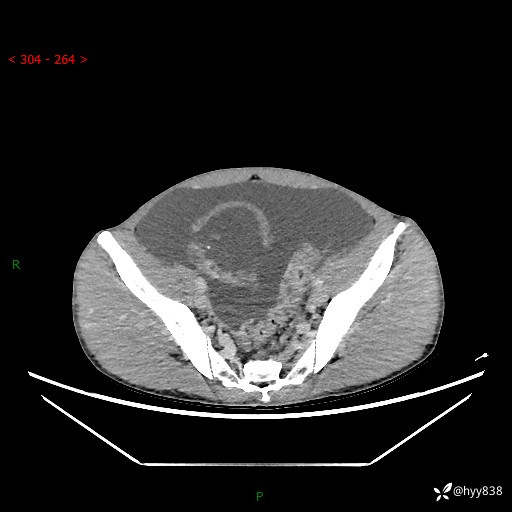

现病史:患者10天前无明显诱因出现腹部胀痛不适,无畏寒发热,无胸痛胸闷,无心慌气短,无恶心呕吐,无腹泻及黑便,无粘液血便及里急后重等症状,4天前在当地县人民医院就诊,行腹部CT示:下腹部占位性病变,腹腔及盆腔积液;今患者为求进一步诊治来我院治疗,门诊以“腹水”收治入院。 发病以来,精神饮食可,大小便正常,体重体力无明显变化。

腹部CT平扫+增强